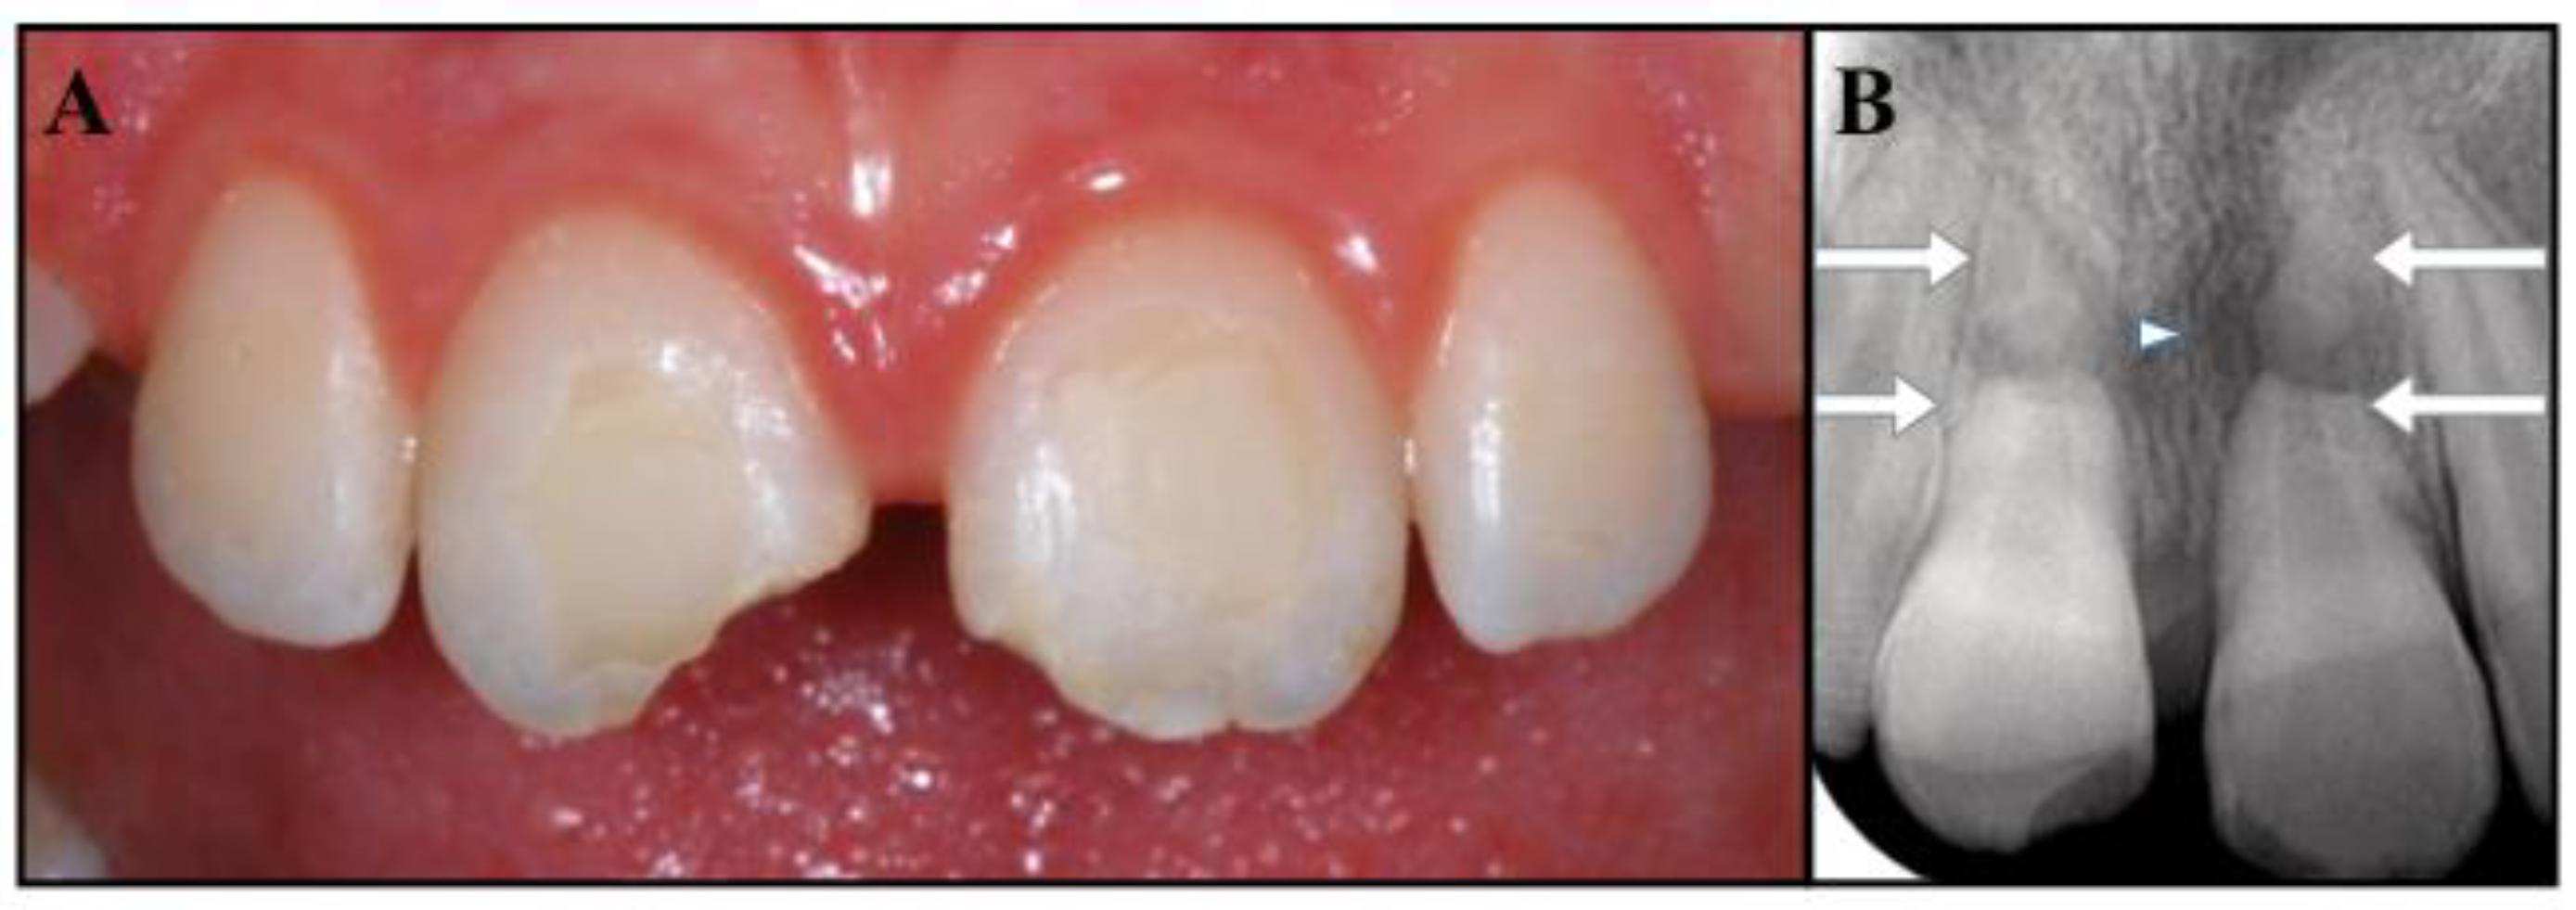

Figure 1.

(A) Clinical photograph showing the uncomplicated crown fracture of the incisal third of teeth #1.1 and #2.1. (B) Periapical radiograph showing the apical root fracture of teeth #1.1 and #2.1 (arrowed) and the radiolucency at the fracture line of #2.1 (small arrow).

The diagnosis was as follows: apical horizontal root fractures of teeth #1.1 and #2.1; severe extrusive luxation of the coronal fragment of both central incisors, which were successfully repositioned; pulp necrosis and chronic apical periodontitis on the coronal portion of tooth #2.1; uncomplicated crown fractures of the incisal third of teeth #1.1 and #2.1. The residual apexes did not show signs or symptoms of apical periodontitis (Figure 1A,B). The prognosis was considered guarded. The proposed treatment was apexification on tooth #2.1 (as the fractured portion of the coronal fragment mimicked an open apex), restoration of the access cavity and of the crown fractures with bonded composite resin, and follow-up of the overall case. The patient and her parents were informed of the diagnosis, treatment plan alternatives, and prognosis of the teeth. Written consent was obtained, and the proposed endodontic management was accepted.